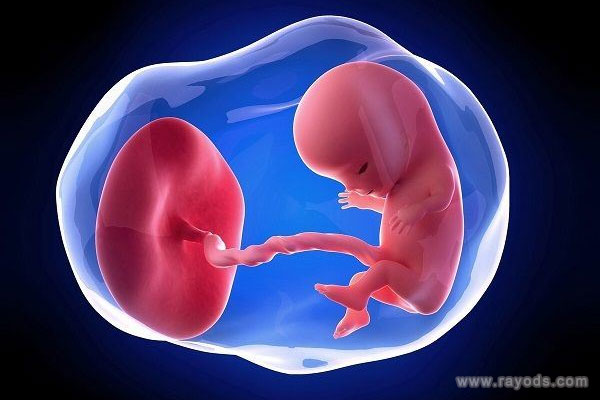

女性正常怀孕后,受精卵着床发育,开始形成孕囊、卵黄囊等,通常卵黄囊的出现时间在孕5周左右,之后会逐渐发育变大,随后胎盘发育又会变小直至消失,所以不同孕周卵黄囊大小通常有一个正常范围,偏大、偏小都需要引起重视。

卵黄囊指的是胎盘组织最原始的物质,对早期胚胎具有非常重要的意义,临床上通过监测其结构、大小等可以判断胚胎是否存在异常,由于每个孕周卵黄囊的大小会发生变化,所以只要处于正常范围都不用过于担心。